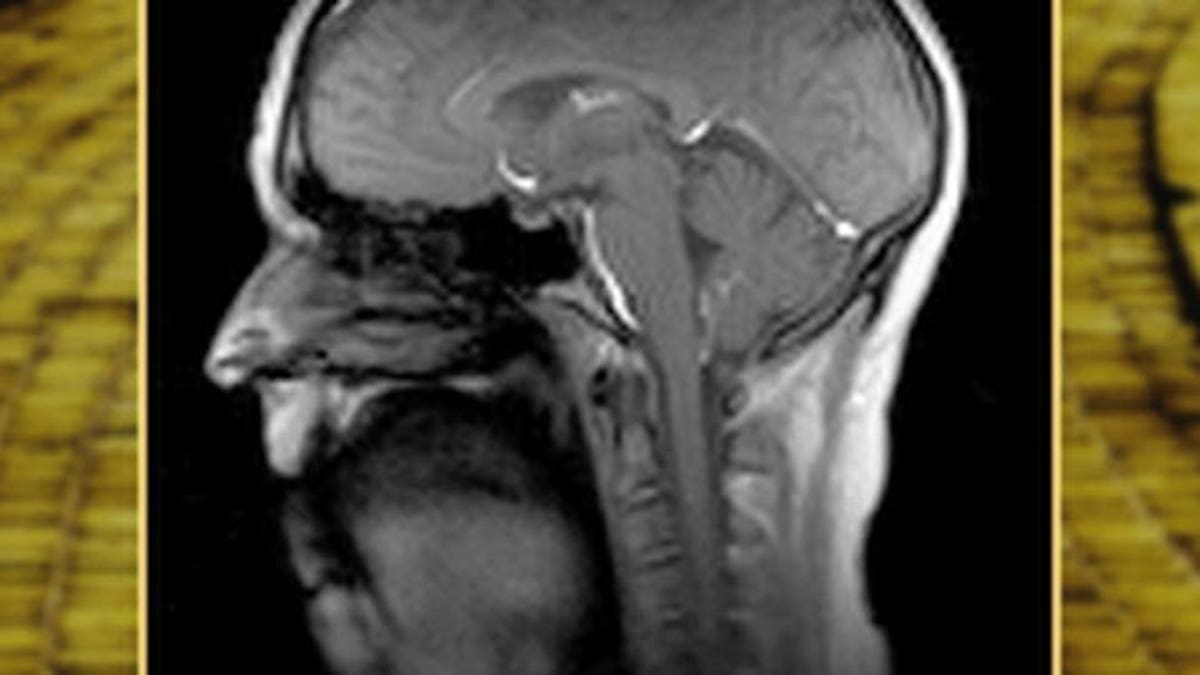

Photo courtesy the Beckman Institute

Using magnetic resonance imaging (MRI) to study how muscles collaborate to produce song and speech has proved challenging for scientists in the past, as typical technology can capture only about 10 frames per second.

. But researchers at the University of Illinois at Urbana-Champaign have overcome that hurdle by inventing a new MRI technology that can scan 100 frames per second without compromising image quality.

The dynamic imaging has helped researchers analyze how about 100 different muscles in the chest, neck, jaw, tongue and lips coordinate, and change over time, to produce sound. Electrical and computer engineering professor Zhi-Pei Liang's group at the Beckman Institute developed the basis for the method.